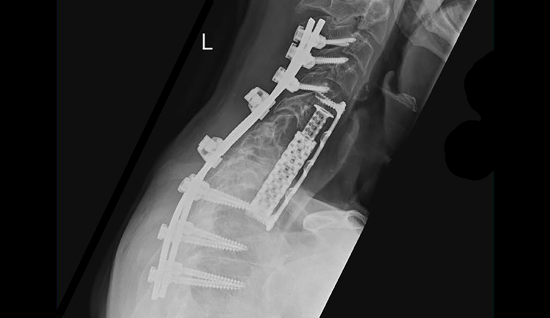

Postoperative X-ray: Posterior corrective spondylodesis C3, 4, 5 to T3, 4, 5 and posterior decompression C6, 7, T1, tumor resection with neon³ and vertebral body replacement C6, C7, T1, T2 with ADD anterior plate osteosynthesis C5 to T3